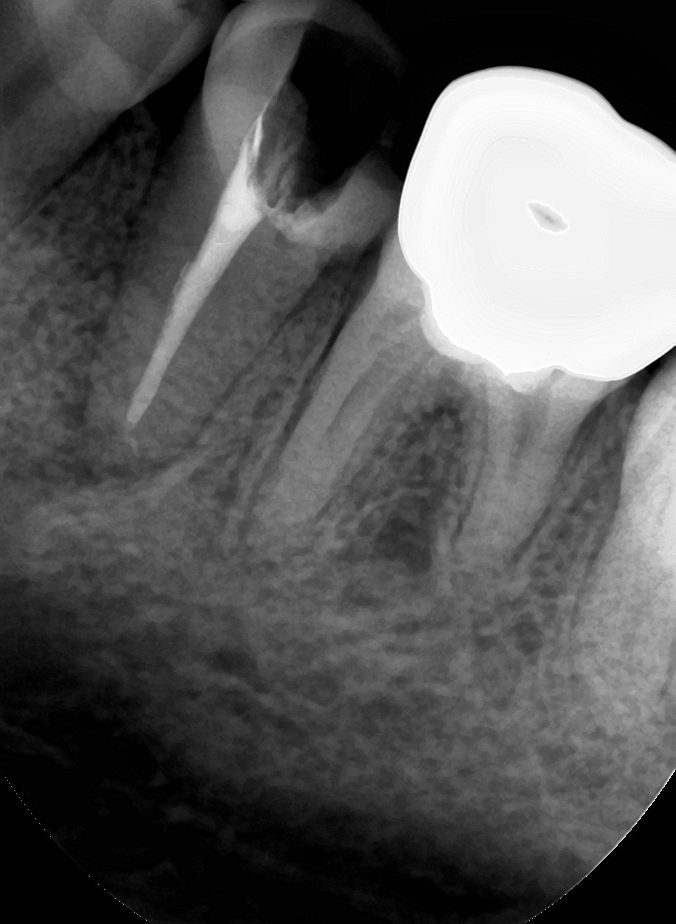

#17 팔라탈 2캐널 케이스 / #46 디스탈 3캐널 케이스

윗줄 사진 두 장은 블로그, 12주차 페닥일기에서 언급했던 상악 제2대구치 팔라탈치근 2개인 치아 임상사진이다. 예상했던 위치 근처에서 실제로 팔라탈 근관 하나를 더 찾았다.

그리고 아래 두 장은 블로그에 올리지는 않았었지만, 저번 주에 기존 크라운 벗겨낸(그래서 프렙이 돼있다) 하악 제1대구치. 디스탈 근관 2개 다 찾았는데 드러난 DL치근 위치가 너무 돌출되어 있어서 해당 위치에 근관이 하나 더 있을 것으로 예상했었다. 그래서 이번 주 예약에 엔도Z버로 확장해 보니 실제로 근관 하나가 더 나왔다. 사실 이 치아는 처음엔 근관 찾으려고 찍은 사진이 아니고, 크라운 벗기고 AO 하니까 와동 바닥에 타DC에서 퍼포 시켜놓고 리페어를 했는지 도대체 알 수가 없는 치질 아닌 웬 이상한 게 있어서 찍어놓은 것이다. 근데 이게 뭘까~ 하고 사진을 가만 보다 보니 갑자기 디스탈에 근관 하나 더 있을 것 같아서 체크해놨었던 케이스.

보통 하악 제1대구치가 5캐널이면 메지알에 MM캐널이 있어서 5캐널인데, 이거는 디스탈에 DM캐널이라고 해야되나, DB2라고 해야되나 아무튼 그게 있고 DL이 멀찌기 떨어져있는 증례였다. 간단히 논문 찾아보니 mandibular first molar에 middle distal canal 가지고 쓴 case report가 몇개 보이긴 하네.